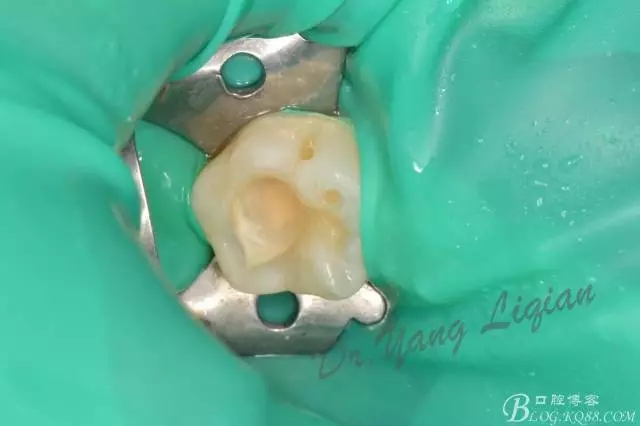

樹脂充填一例

640.webp (5).jpg

640.jpg

640.webp (6).jpg

640.webp (7).jpg

640.webp (8).jpg

640.webp (9).jpg

640.webp (10).jpg

640.webp (11).jpg

640.webp (12).jpg